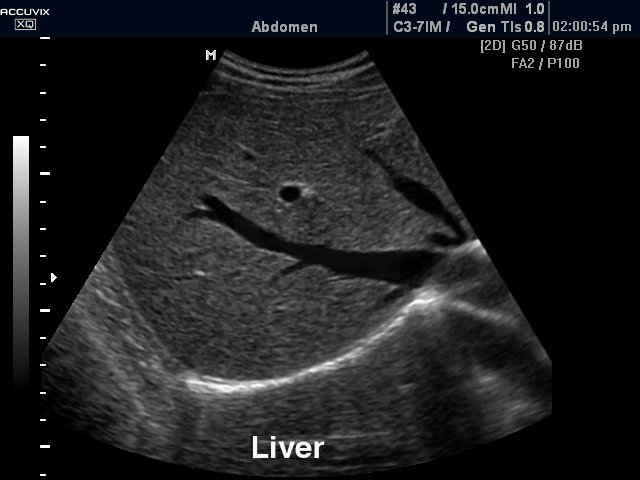

- Υπέρηχος άνω και κάτω κοιλίας

- Υπέρηχος άνω κοιλίας κατ’ οίκον ( ήπαρ, χοληδόχος κύστη, χοληφόρα, πάγκρεας, σπλην, νεφροί )

- Υπέρηχος άνω και κάτω κοιλίας κατ’ οίκον σε άντρα ( ήπαρ, χοληδόχος κύστη, χοληφόρα, πάγκρεας, σπλην, νεφροί, ουροδόχος κύστη, προστάτης)

- Υπέρηχος άνω και κάτω κοιλίας κατ’ οίκον σε γυναίκα ( ήπαρ, χοληδόχος κύστη, χοληφόρα, πάγκρεας, σπλην, νεφροί, ουροδόχος κύστη, μήτρα, ωοθήκες)